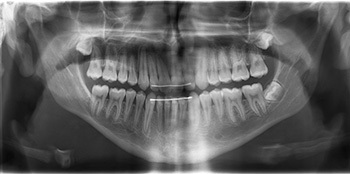

Initially, I started with upper braces only and a Class 3 bite ramp (Fig. 3) to disclude and simulate (b) See my previous article on Class 3 ramps in last month’s issue of Orthotown. Four months later (Fig. 4), lower braces were put on, and I bonded caplin hooks to the lingual of all molars for full-time (alternating crossbite pattern) vertical elastics to erupt the posterior teeth to meet the new vertical goal of (b).

Alternating crossbite pattern vertical elastics to lingual caplin hooks is the best way to erupt posterior teeth without changing their inclination as they extrude. If I had to do it over again, I would have started with these vertical elastics from Day One. The patient did a great job with the vertical elastics, and at month seven (Fig. 5) the molars were in contact, and the bite ramp was removed.

At this point Ethan’s new vertical position matched (b), and the molars had erupted into contact to support this position. The vertical elastics continued, now just at night, through most of his remaining months in treatment to prevent relapse of the extruded molars and loss of the new vertical position. Some Class 3 elastics were used as well, but vertical elastics were the most heavily used.

Figure 6 shows progress through month 16. Upper incisors were not flipped, and SAP bracket positioning (à la Tom Pitts) was used to cheat the occlusal plane in favor of more upper incisor show (Class 3 patients are quite often deficient in vertical incisor show). A noticeable change in the occlusal plane is apparent on cephalometric comparison, reflective of this SAP bracket positioning. This increased vertical incisor show is expressed well within his now decompensated (taller) smile window allowed by (b).

The case finished in 21 months (Figs. 7–10). Ethan will be monitored until growth is complete, and he and his mom are aware of the possibility of relapse if remaining growth is unfavorable.